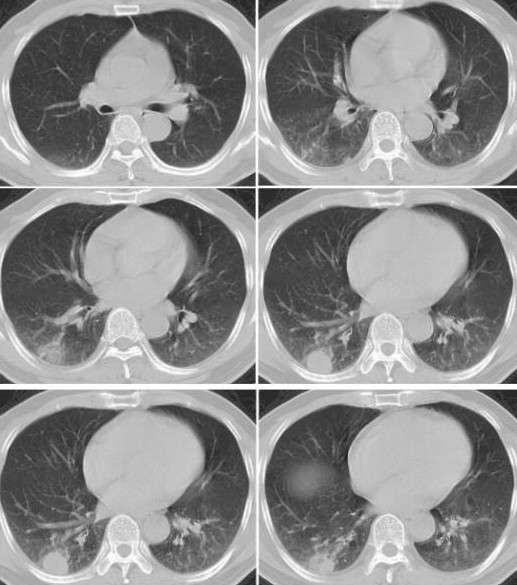

病例挑战:肺单发类圆形病变---球形肺炎

图6球形肺炎

公布结果:患者经抗感染治疗5天后复查ct,阴影基本消失,支持 球形肺炎!